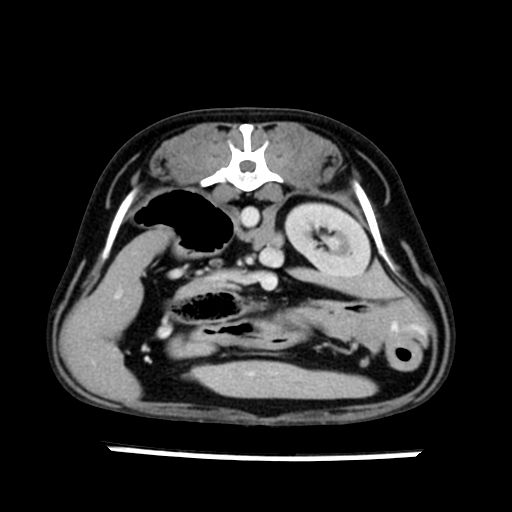

prescritto esame TAC

sequenza immagini limitata al fegato reni e surreni

le immagini ecografiche rispetto alla tac datano circa 7 mesi prima ,le surrenali sono normali nonostante il test acth sia risultato positivo .all’esame TAC dopo diversi mesi risultano aumentate armonicamente nel volume e si individua un forte sospetto di adenoma ipofisario .

sospetto adenoma ipofisario vs. meno probabilmente meningioma della base; intertiziopatia polmonare; lesione espansiva epatica, verosimilmente del lobo laterale sinistro, di sospetta natura neoplastica; lesioni spleniche di natura da definire; iperplasia/ipertrofia delle ghiandole surrenali, bilateralmente; vertebra di transizione del rachide toracico; tenosinovite cronica del muscolo bicipite brachiale di destra.